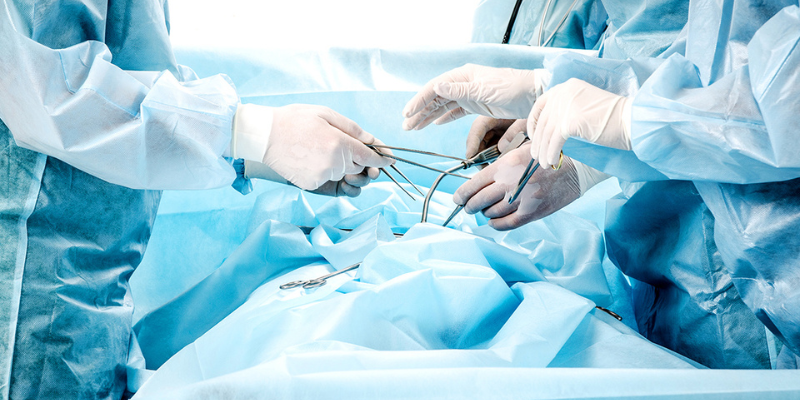

At Dhanvantri Multispeciality Hospital, our Department of Orthopaedics delivers world-class care for a wide spectrum of musculoskeletal conditions. Whether you’re suffering from chronic joint pain, recovering from a sports injury, or experiencing a traumatic fracture, our team of highly experienced orthopaedic surgeons, spine specialists, and physiotherapists is here to help you regain mobility and live pain-free.

Our orthopaedic services combine advanced surgical techniques, modern diagnostic tools, and holistic rehabilitation to provide patients with safe, effective, and personalized treatment plans. From joint replacements to minimally invasive arthroscopy, and from complex spine surgeries to emergency trauma care, we cater to patients of all ages with precision and compassion.